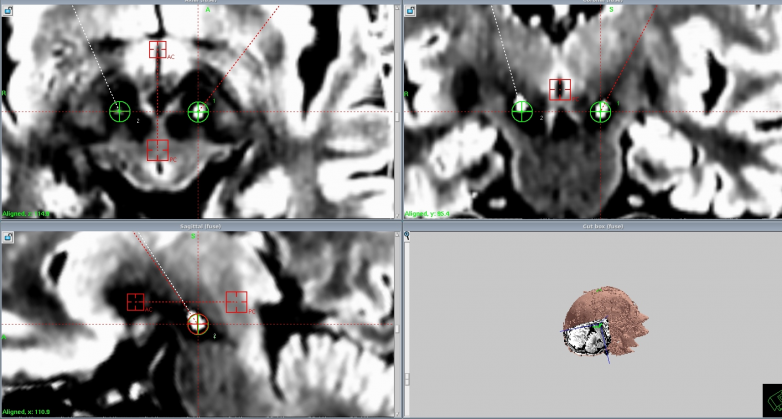

计伟主任带领手术团队,以精湛的技艺和严谨的态度投入到手术操作中。他们借助先进的影像导航技术,精准定位核团靶点,每一个操作都小心翼翼、精准无误。在植入设备的过程中,手术团队密切配合,精细操作,确保电极准确无误地植入到预定位置。整个手术过程紧张而有序,手术最终顺利完成。术后患者各项生命体征平稳,神志清醒,肢体活动良好,颅脑CT及各项检查均未见异常,手术取得了圆满成功。

可充电、可感知闭环脑起搏器Percept™ RC工作原理示意图